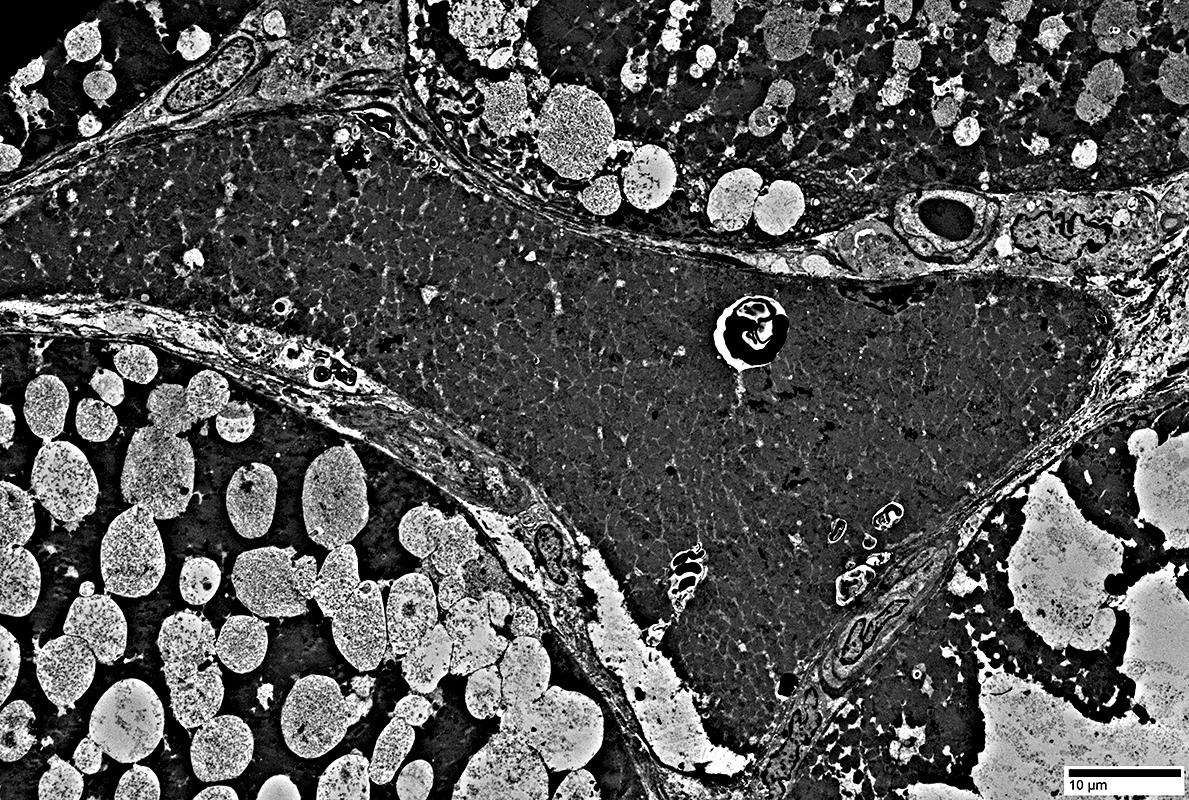

Autophagic Vacuoles

Multiple small vacuoles in small muscle fiber (Yellow arrow)

Large autophagic vacuole: Budding from the surface of a large muscle fiber (White arrow)

Multiple small vacuoles in small muscle fiber

Lymphocytes

Location: Endomysium; Surround muscle fiber

Large vacuole replacing most cytoplasm in small muscle fiber (Above)

Contents of vacuole (Below)

Autophagic Vacuoles: Different contents

Filaments: Varied densities

Myeloid figures

Aggregates

From: R Schmidt